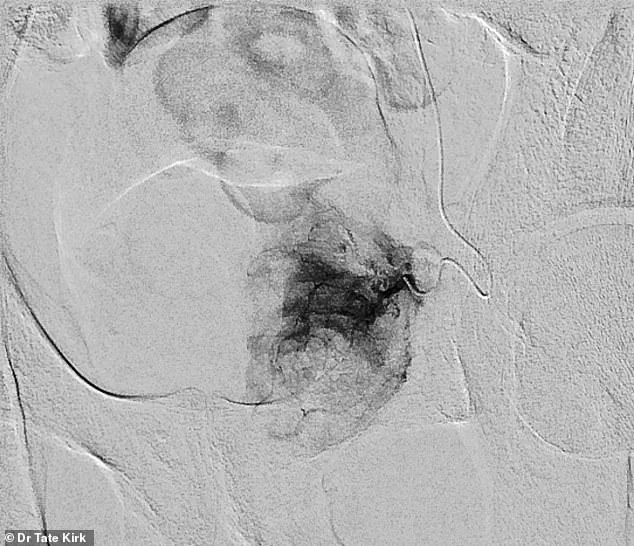

Pre-embolization, a catheter is carefully threaded into the artery supplying blood to the left half of the enlarged prostate, a step that requires precision and expertise.

Post-embolization, the artery is effectively sealed off, halting blood flow to the prostate tissue.

This targeted approach not only reduces the size of the prostate but also minimizes damage to surrounding structures, a critical advantage in a procedure that is rapidly gaining favor among patients and specialists alike.

Using real-time X-ray imaging, the physician navigates the catheter with precision, delivering tiny particles to block blood flow to the prostate.

This reduction in vascular supply triggers the gland to shrink, alleviating pressure on the urethra and restoring urinary function.